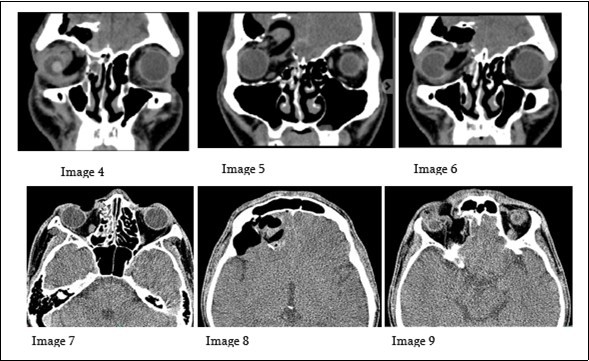

Patient underwent emergency cranial CT SCAN with orbital cuts to evaluate the extent of the injury. Figure 2.

Figure 2.The images (4-6) on the upper row, are serial coronal cuts of the cranial CT scan done for the patient. While images on the lower row (7-9) are axial cuts of the same scan.

The images (4-6) on the upper row, are serial coronal cuts of the cranial CT scan done for the patient. While images on the lower row (7-9) are axial cuts of the same scan.

There is a barrel shaped hypodense foreign body, seen to enter the anterior and medial aspects of the right orbit. The aforementioned foreign body is directed superiorly and is seen traversing or penetrating the right superior orbital wall, right medial lamina papyracea and the lateral and inferior border of the right frontal sinus, with its distal tip at the intracranial region at the right frontal lobe. There are fractured fragments, likely from the comminuted superior orbital wall and seen within the right frontal lobe. Along its track, it compresses the right globe and the right medial rectus muscle. Pneumocephalus in the right frontal convexity was noted and hemosinus in the right frontal and ethmoid sinus are likewise observed. Prolapse of the right medial orbital fat into the ipsilateral ethmoid sinus is noted.